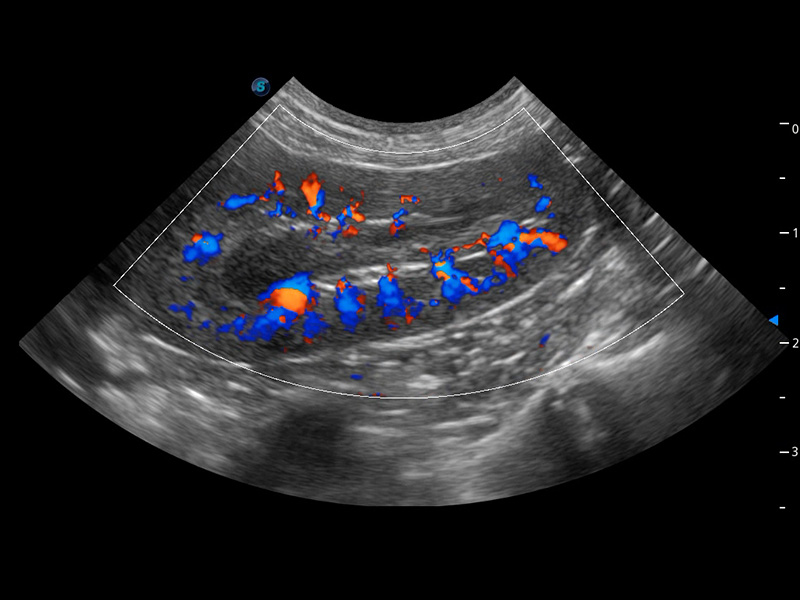

ProPet 60 作为一款高端台式动物超声设备,为动物医生的日常诊断提供了一系列贴合动物临床需求、解决临床实际问题的高级成像功能。凭借全系列高清探头,满足医生对腹部、心脏、生殖、浅表、肌骨等成像的所有需求,切实帮助您提升检查效率,提高诊断信心。

兽用彩色多普勒超声诊断系统

动物是人类最亲密的朋友和最值得信赖的伙伴。乐玩lewin国际也一直致力于探索动物专用的超声影像解决方案。 全新推出的ProPet系列,是乐玩lewin国际在动物超声影像智能化、专业化、精准化的一次跨越式革新。动物不能用言语来表述自己的不适,通过超声影像,ProPet系列搭建了动物医生与不同物种沟通的“桥梁”,为动物医生注入了“治愈之力”。